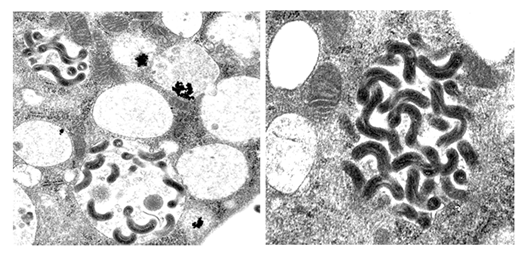

細菌学講座では本菌の病原因子の同定とその機能解析を行い、レプトスピラ症に対するワクチン開発や迅速診断法の開発の手がかりとなる基礎的知見の確立を目指す。これまでに、自然免疫系細胞のマクロファージ機能に着目し、病原性レプトスピラがマクロファージに貪食後、ファゴソーム内で生存できることを明らかにした(図)。現在、レプトスピラの研究が多方面に発展しており、トランスポゾン挿入変異体ライブラリーを用いた解析、DNAマイクロアレイを用いた解析やマウス感染モデルを用いた腎臓持続感染機構の解析を行っている。

ファゴソーム内で生存できるレプトスピラの電子顕微鏡像